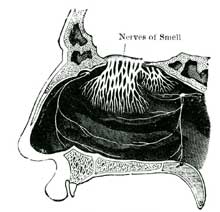

| XXV. | How we Hear, See, Smell, Taste; and Feel | 138 |